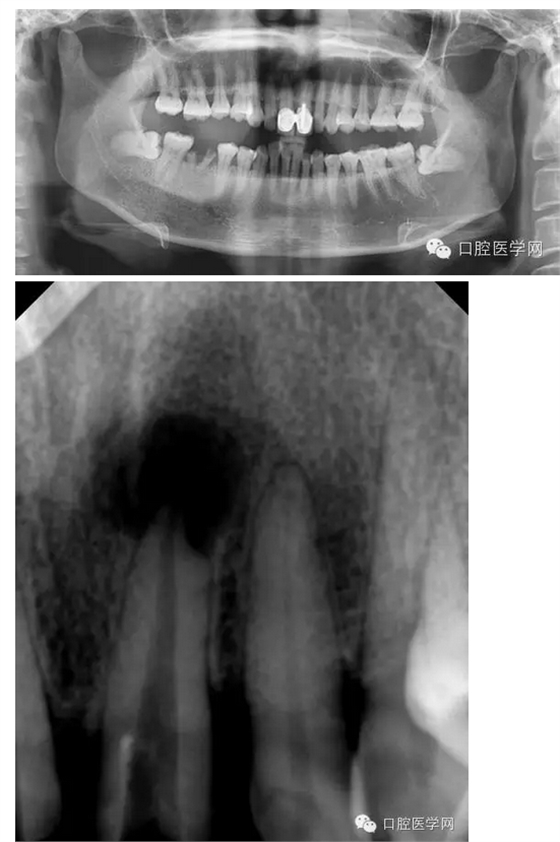

輔助檢查:21x線示根周有大面積陰影